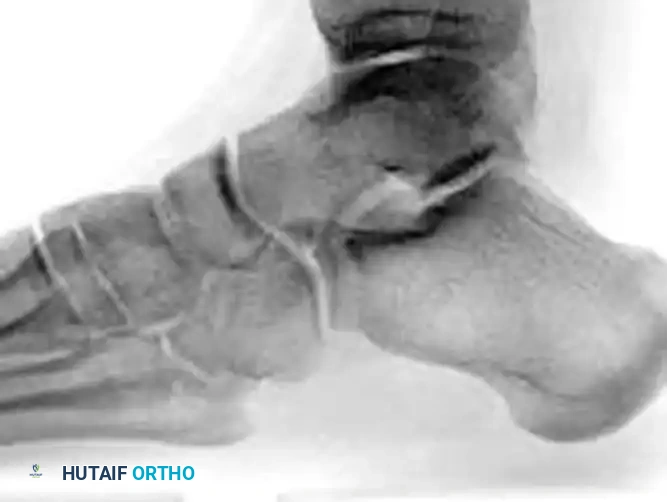

• Radiographic Evaluation: Plain radiographs (AP, lateral, and oblique views of the foot and ankle) may define the fracture clearly. However, overlapping osseous structures often obscure the true extent of the injury.

• Advanced Imaging: Computed Tomography (CT) is considered mandatory for definitive diagnosis, evaluation of displacement, assessment of intra-articular comminution, and preoperative planning.

Image

SURGICAL MANAGEMENT OF TALAR HEAD FRACTURES

The primary goals of treatment are to restore the congruity of the talonavicular joint, maintain the length of the medial column, and preserve the tenuous vascular supply to the talus.

Indications for Operative Intervention

• Displaced Fractures: Any displacement greater than 1-2 mm, particularly shear-type injuries, warrants Open Reduction and Internal Fixation (ORIF).

• Impacted Fractures: Articular impaction leading to joint incongruity requires elevation and bone grafting.

• Instability: Fractures associated with subluxation or dislocation of the talonavicular joint.